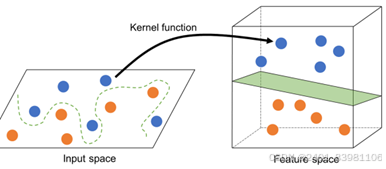

RGB、Lab、HIS、YCrCb测量可视化颜色,利用RGB和CIE实验室颜色模型之间的转换关系,得到离散色谱分布

不同边缘颜色值主成分因子载荷分布

问题:b*颜色转换准确性太差